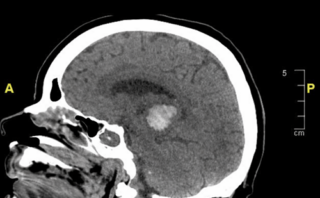

La tomografía de tórax evidencia patrón intersticial difuso bilateral con presencia de lesiones quísticas compatibles con neumatoceles, característicos de infección por Pneumocystis jirovecii.

El desarrollo de SDRA refleja daño alveolar difuso, mientras que la formación de neumatoceles condiciona fragilidad estructural pulmonar. La ventilación mecánica, aunque necesaria, incrementa el riesgo de ruptura alveolar, desencadenando barotrauma.